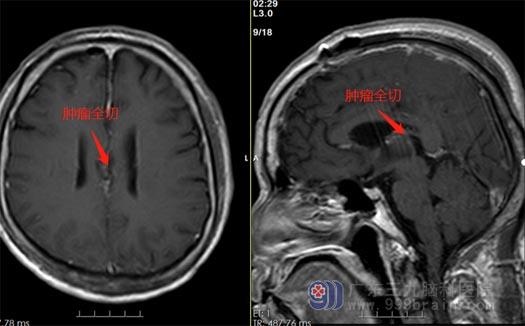

▲术后

考虑到患者比较惧怕手术,鲁明和神经外五科王国良主任带领团队进行讨论,一致认为需要进行双额部大脑镰脑膜瘤切除术,由鲁明主刀、贺小军主治医师协助,在显微镜下全切了肿瘤,手术对双侧腁周动脉、脑组织保护完好。术后,区叔没有出现并发症,满意出院。